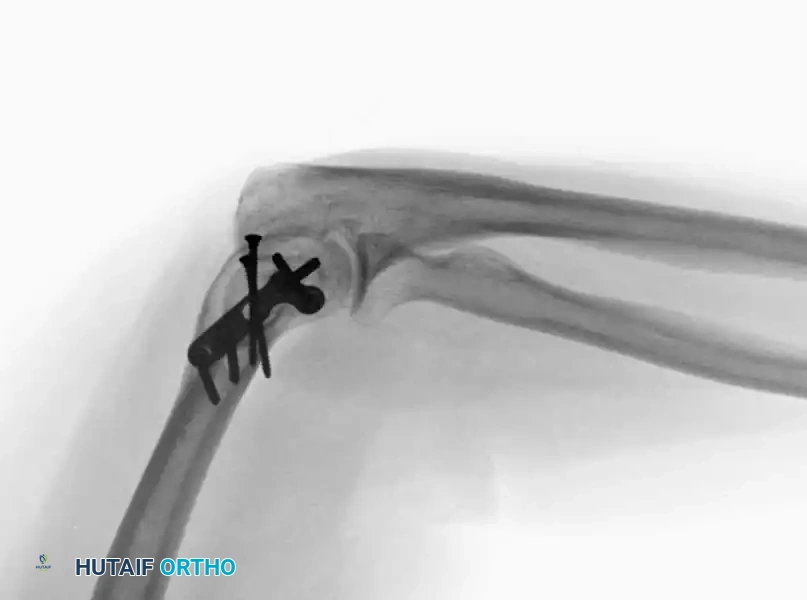

Image

Fig. 5: Intraoperative and radiographic views demonstrating robust bicolumnar parallel plating.